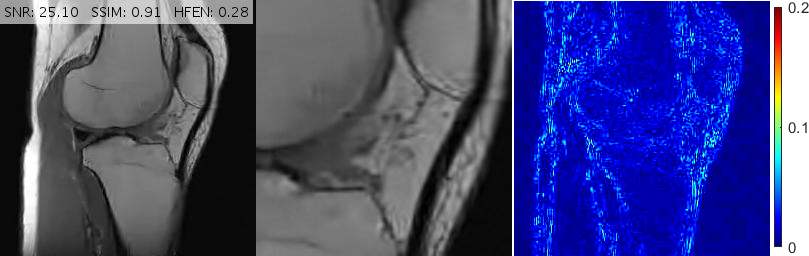

Fig. 6 depicts the reconstruction results for above setups. As attested by the magnified views and error metrics inserted to the top of each reconstruction, TV and TGV significantly degrade the reconstructed image in the rotated setup while RITV gives a remarkably consistent and high-quality result which is hardly distinguishable from the upright solution (note that HFEN and SSIM indices do not change in RITV after rotation). Of course, the upright and rotated directions are only chosen relatively and can always be swapped, nevertheless, the point is TV and TGV fail in at least one of the orientations while RITV succeeds in both. Note that if the selected MR image and Cartesian mask are denoted by and respectively, then a simple machine-aided computation shows that . Therefore, even though the norm-preserving assumption of Theorem 2.1 does not hold true in this experiment (and in fact in many practical situations), the result of RITV is still incredibly isotropic.

Fig. 10 shows the performance of various algorithms for a sagittal head scan reconstruction under 16% spiral sampling. The solutions provided by pFISTA and TL miss much of the image content due to over-smoothing. TGV+Shearlet leaves many incoherent artifacts on all regions. The magnified views obviously show that BM3D degrades the image by leaving block artifacts around the cerebellum and streaking artifacts on the medulla and the visual cortex. DAMP, GBRWT, ADMM Net and FDLCP provide more accurate results, however, by inspecting the magnified views it becomes evident that some small artifacts are introduced in DAMP near the caudate nucleus and beneath the cerebellum while a dark hole at the center of the cerebellum has been almost entirely smoothed out by the other three methods. The proposed method (labeled ‘New’) accurately captures this hole and corrects all the errors mentioned above.

Fig. 11 shows reconstructions for an FSE sagittal knee slice under 16% radial sampling. Solutions provided by TGV+Sh, pFISTA, GBRWT, DAMP and BM3D give rise to incoherent, streaking and block artifacts observable in the magnified views. Deep ADMM Net, TL and FDLCP provide more acceptable results, however, the proposed method gives the best and sharpest reconstruction.

For convenience, in Figs. 10, 11 and 13 we have inserted the SNR, SSIM and HFEN values for each method to the top of the corresponding reconstructed image. Moreover, some reconstruction errors in compared methods and their corrections in the proposed method are annotated with arrows.